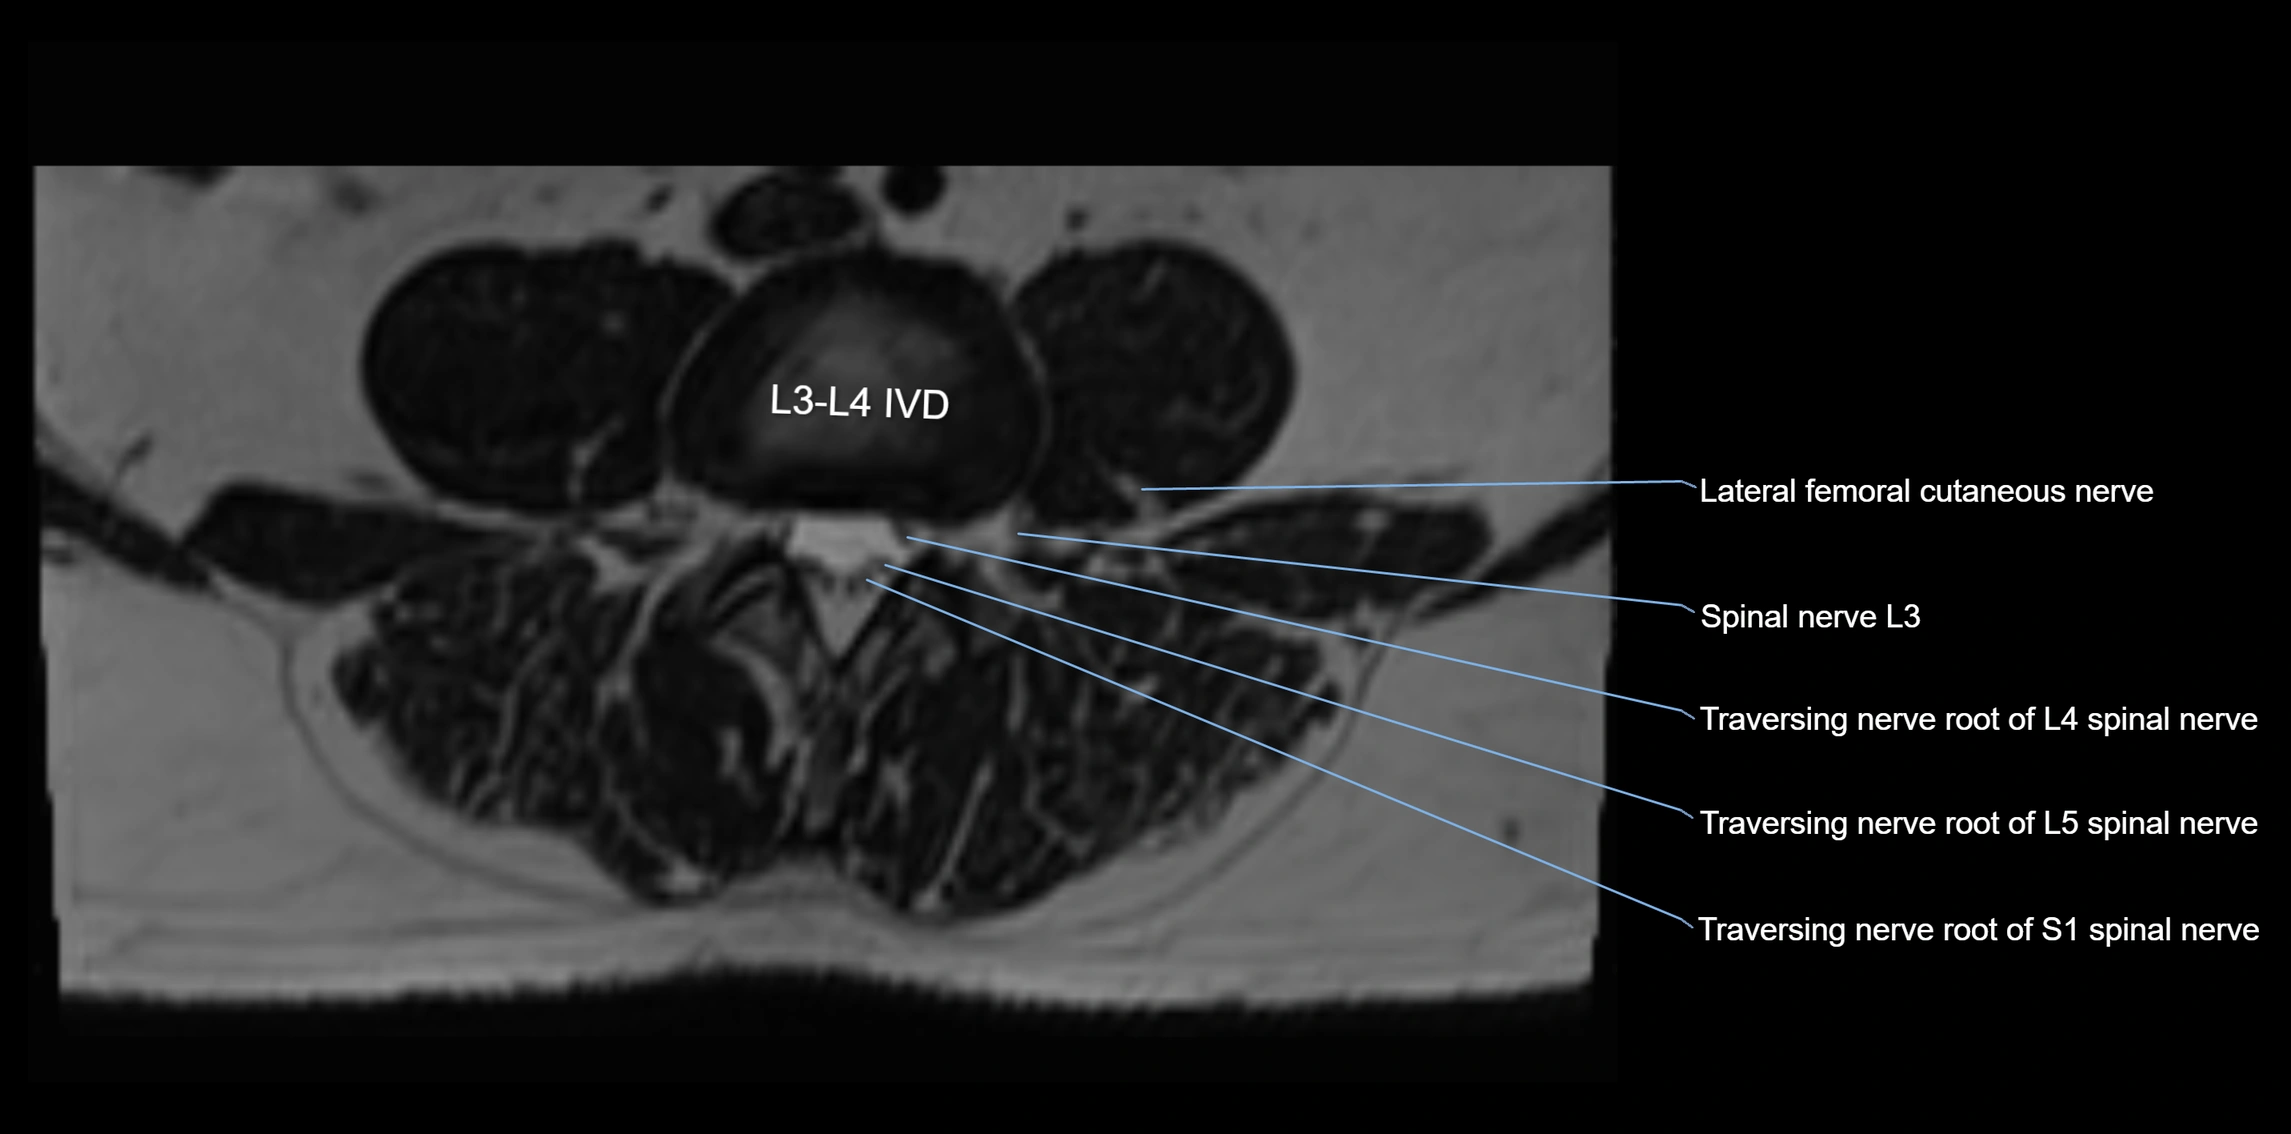

MRI image

image